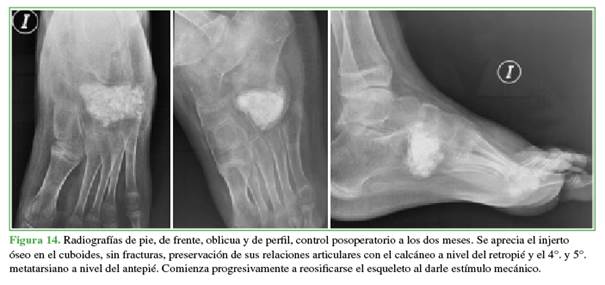

Se permitio el apoyo parcial al mes de la cirugia y comenzar a aumentar la carga, progresivamente, cada semana. El seguimiento se realizó dos veces por mes, los primeros seis meses (Figuras 13-15) y, luego, al año, porque el

paciente no pudo concurrir a los controles por motivos personales (Figuras 16 y 17).